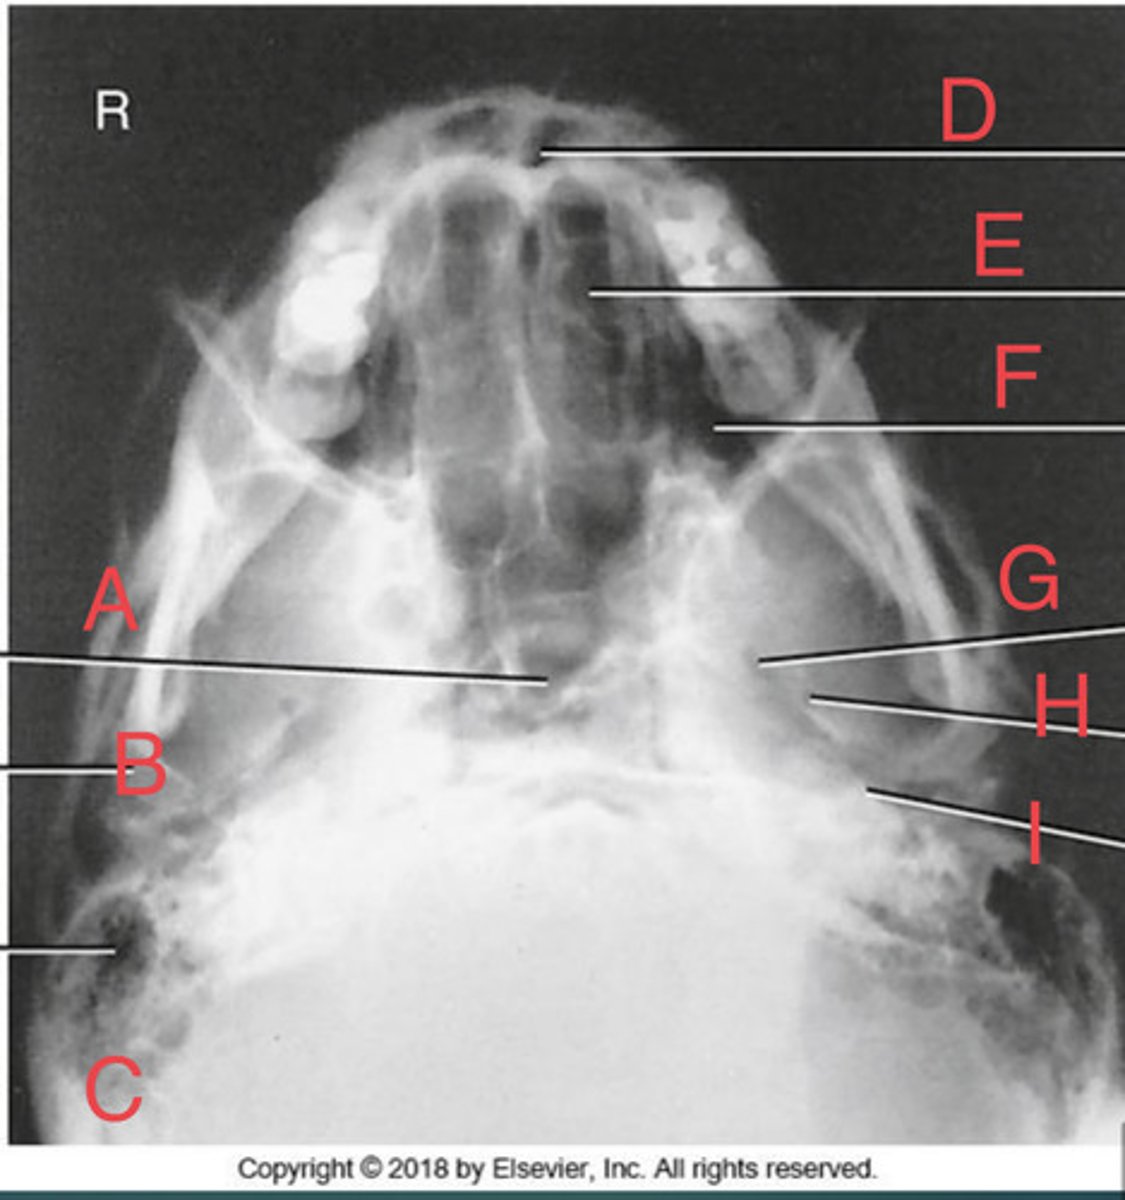

SMV sinuses

What position?

Sphenoid sinus of sphenoid bone

A.

R mandibular condyle of mandible

B.

R Mastoid air cells of temporal bone

C.

Nasal fossa

D.

L. Ethmoid sinus of ethmoid bone

E.

L maxillary sinus of maxilla

F.

L foramen ovale of sphenoid bone

G.

foramen spinosum of sphenoid bone

H.